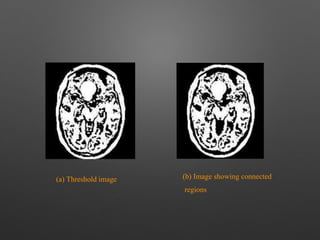

(a) Threshold image (b) Image showing connected

regions

(a) Threshold image(b) Image showing connected regions